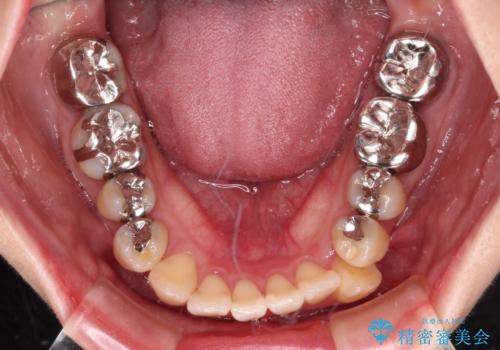

- 前歯のデコボコとセラミッククラウン周りの黒い縁を気にして来院された患者様です。

ワイヤー装置、マウスピース、どちらの装置でも治療は可能でしたが、マウスピース矯正の自己管理の煩わしさを懸念され、ワイヤー装置にて矯正治療を行うこととしました。

前歯の黒い縁は、矯正治療後にオールセラミッククラウンにて改善することとしましたが、いち早く目立たなくしたいとのことで、事前に矯正治療用仮歯に置き換えてから矯正治療を開始しました。